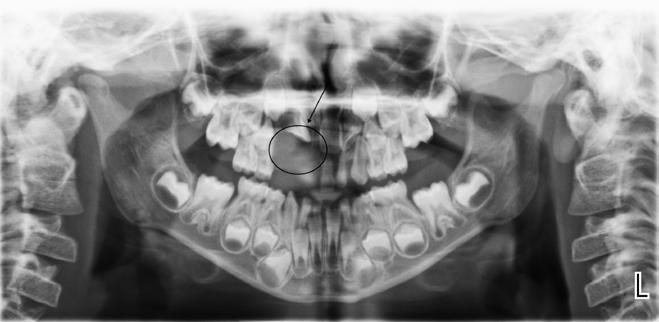

overbid (VOB). Papillen mellem 1+1 er betydeligt reduceret pga. fæstetab, og de mesialt kippede 1+1 har resulteret i en ”dark triangle”. Den facioorale funktion er for nuværende i.a. Panoramarøntgen (Fig. 1, I) viser marginalt knogletab i begge kæber og fravær af 8,7+7,8 og 8,7-8.

Objektivt anbefales behandling af det dybe bid, som ubehandlet forventes at forværres yderligere over tid. Patienten har ønske om behandling med æstetisk ortodontisk apparatur, alignere, og det vurderes muligt at behandle malokklusionen med alignere. Dog anbefales det generelt, at alignere undgås eller benyttes med væsentlige modifikationer af alignerens retention ved tandmobilitet, da dette ellers kan medføre jiggling, når aligneren tages af og på mange gange dagligt. På den anden side er der nogen evidens for, at alignerbehandling er associeret med bedre renhold og parodontal sundhed sammenlignet med fast apparatur (16).